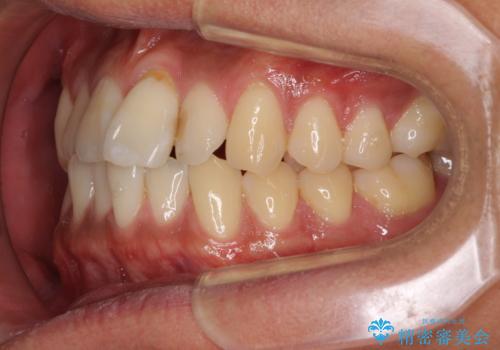

気になる前歯のデコボコをインビザラインで解消

- 前歯のデコボコを気にして来院された患者様です。

主に下顎歯列全体の後方移動とIPR(歯と歯の間を削る)によってデコボコが解消するように設計し、インビザラインにより治療を行うこととしました。

インビザライン矯正特有の、治療後半で前歯のみが強く接触する症状が発現し、咬み合わせ改善に期間を要することとなりました。